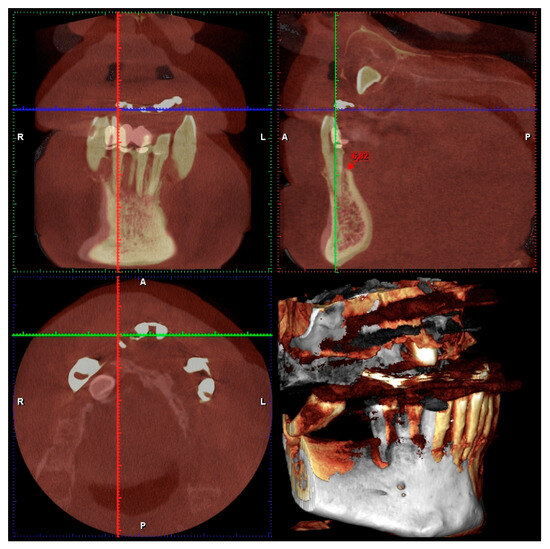

| J.C.—72 | J.C. | 43 | 2 | EXTR 4F | 4 mm | 4 min | 6.82 | 5.48 |

| J.C.—72 | J.C. | 42 | 2 | EXTR 2F | 4 mm | 5 min | 6.28 | 4.89 |

| J.C.—72 | J.C. | 41 | 2 | EXTR 2F | 4 mm | 2 min | 5.69 | 3.92 |

| J.C.—72 | J.C. | 31 | 2 | EXTR 2F | 4 mm | 3 min | 5.56 | 3.8 |

| J.C.—72 | J.C. | 32 | 2 | EXTR 2F | 4 mm | 2 min | 6.42 | 4.75 |